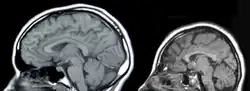

There are four main causes of CNS injury: stroke, traumatic brain injury (TBI), brain tumors, or developmental complications. Strokes are classified as either hemorrhagic (when a vessel is damaged to the point of bleeding into the brain) or ischemic (when a clot blocks the blood flow through the vessel in the brain). When a hemorrhage occurs, blood seeps into the surrounding tissue, resulting in tissue death, while ischemic hemorrhages result in a lack of blood flow to certain tissues. Traumatic brain injury is caused by external forces impacting the cranium or the spinal cord. Problems with CNS development results in abnormal tissue growth during development, thus decreasing the function of the CNS.[16]

Normal Brain Development (left), Microcephaly, a type of encephalopathy (right)